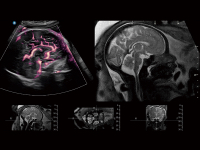

豐富的血流動(dòng)力學(xué)檢測(cè)技術(shù),可在不同醫(yī)療場(chǎng)景中高效捕捉血流信號(hào),助力臨床診療。

在傳統(tǒng)血流的基礎(chǔ)上優(yōu)化掃查和算法策略,能夠更好的抑制組織信息,提煉紅細(xì)胞運(yùn)動(dòng)信息,得到更高幀頻,高靈敏度和分辨率的血流信號(hào),還原更真實(shí)的血流動(dòng)力學(xué)。

通過光照模型,使二維血流顯示出立體的效果,增加血流的敏感性、成束性,減少外溢??梢院推渌煌难骷夹g(shù)聯(lián)合使用,融合不同技術(shù)的優(yōu)勢(shì)。輕松應(yīng)對(duì)微小血管,增強(qiáng)血流的立體效果,提升視覺敏感性。

通過創(chuàng)新的Matrix E自適應(yīng)濾波算法,能有效濾除軟組織和噪聲信號(hào),最大限度保留超低速微細(xì)血流的信號(hào);結(jié)合超長時(shí)間域算法,極大提升細(xì)微血流的敏感性和空間分辨率,更真實(shí)的反應(yīng)組織、包塊的血流灌注情況。